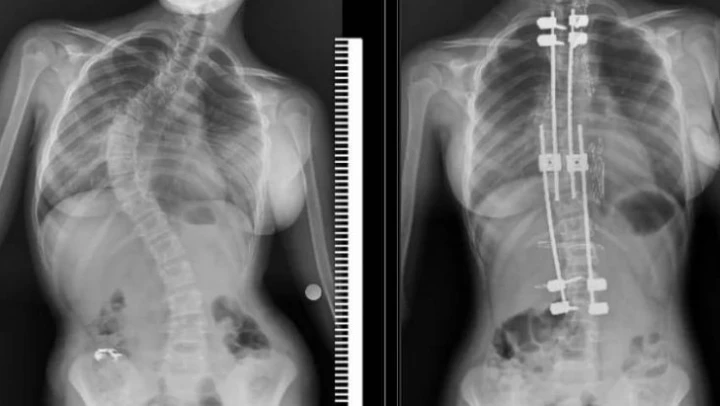

Samsun'un Bafra ilçesinde yaşayan 10 yaşındaki Zümra Demircioğlu bel ve sırt bölgesinde aşırı ağrı ve günlük aktivitelerini yapmakta zorlanma şikayetleri nedenleriyle Samsun Eğitim ve Araştırma Hastanesi'ne başvurdu. Burada çekilen röntgen ve yapılan tetkikler sonucunda 75 derece omurga eğriliği tespit edilen minik Zümra için ameliyat kararı verildi. Büyüme koruyucu sisteminin uygulandığı ameliyatta minik Zümra'nın omurgası düzeltildi. Özel hastanelerde ortalama 300 ile 500 bin TL arasında yapıldığı öğrenilen bu ameliyat artık Samsun Eğitim ve Araştırma Hastanesi'nde ücretsiz olarak gerçekleştiriliyor.

Ameliyat hakkında bilgi veren Dr. Ömer Bozduman, 'Bu gibi durumlarda uzayan rot dediğimiz bir sistem uyguluyoruz. Bunun nedeni çocukları yaşı küçük olduğu için füzyon dediğimiz kaynatma ameliyatı yaparsak akciğerlerinde yetersiz gelişme, göğüs kafeslerinde yetersiz gelişme ve kanallarında yetersiz gelişme oluşabileceği için büyüme koruyucu cerrahi yapıyoruz. Büyüme koruyucu cerrahinin diğer füzyon cerrahisinden alternatifi şudur: Düzenli aralıklarla düzeltme yapıyoruz. Çocuk büyüdükçe biz de bu sistem anestezi altında ya da anestezisiz olarak uzatarak çocuğun yeterli omurga büyüklüğüne ulaştıktan sonra yeterli kalıcı ameliyatı gerçekleştiriyoruz. Anestezi hocamız Doç. Dr. Serkan Turgal yardımı ile bu ameliyatı başarıyla gerçekleştirdik. 10 yaşındaki hastamıza büyüme koruyucu sistemi yerleştirdik. Düzenli aralıklarla uzatmalarını yapacağız. Nihai ameliyatını omurgası büyüdükten sonra gerçekleştireceğiz. Eğitim ve Araştırma Hastanesi olarak bir ilki gerçekleştirdik. Hastamız gayet iyidir. Birinci günün kalkıp yürüdü. Dördün gün sonra taburcu ettik. Herhangi bir nörolojik veya başka bir sorunla karşılaşmadık. İhtiyacı olan tüm hastalarımıza Samsun Eğitim ve Araştırma Hastanesi olarak devletimizin imkanlarıyla bu hizmeti ücretsiz olarak veriyoruz. Aileler bu semptomlar hakkında dikkatli olmalıdır. En ufak şüphede polikliniklerimize bekliyoruz. Bizler yardımcı olacağız' diye konuştu.